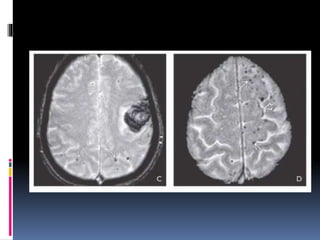

FLAIR (left) and GRE (right) in the same case show HT in this example of subacute

stroke

AxialT1WI at 2 weeks after stroke onset shows

hemorrhagic BG transformation , persisting

gyral swelling with sulcal effacement

T1 C+ FS scan in the same patient shows

intense enhancement characteristic of subacute

infarction

FLAIR (left) andGRE (right) in the same case show HT in this example of subacute stroke

AxialT1WI at 2weeks after stroke onset shows hemorrhagic BG transformation , persisting gyral swelling with sulcal effacement T1 C+ FS scan in the same patient shows intense enhancement characteristic of subacute infarction